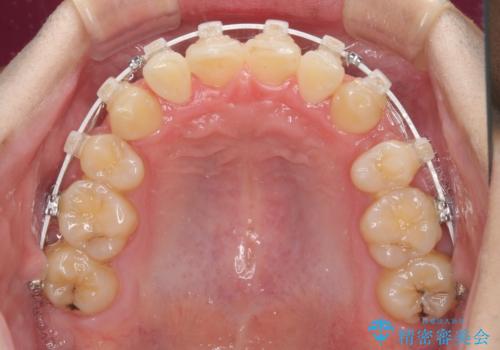

- 矯正装置

- 審美装置

- 結婚式が近いとのことで、前歯のデコボコを改善したいと来院された患者様です。

口元の突出感はないものの、上顎前歯のデコボコが著しかったため、上顎左右第一小臼歯2本を抜歯することとしました。

咬合力が非常に強く、抜歯したスペースがなかなか閉じないであろうことは予想できましたが、思っていた以上に期間がかかりました。

前歯のすり減りも著しかったため、仕上げの位置の調整にも期間を要しました。